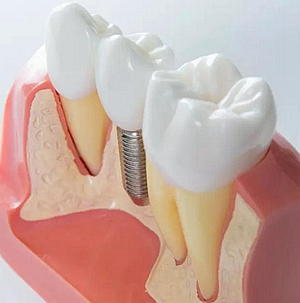

上頜后牙缺失患者常由于先天性上頜竇底位置過低、牙槽骨嚴重吸收、萎縮等原因, 使骨量高度不足。直接植入種植體易穿入上頜竇引起感染等并發(fā)癥, 導(dǎo)致種植失敗。上頜竇底提升技術(shù)(Maxillary Sinus FloorLifting)是采用外科手術(shù)方法將上

頜竇黏膜從竇底剝離后抬高,在竇底黏膜與竇底骨之間植入骨移植材料,有效增加骨的高度,在此基礎(chǔ)上植入種植體,使種植體獲得足夠的高度及初期穩(wěn)定性。

目前骨移植材料多使用生物相容性較好的人工骨粉。根據(jù)手術(shù)方法的不同,上頜竇底提升術(shù)主要分為兩種:上頜竇內(nèi)提升和上頜竇外提升。

針對不同的臨床病例選擇合適的手術(shù)方式。今天我們先看看內(nèi)提升手術(shù)的相關(guān)操作。上頜竇內(nèi)提升種植術(shù),又叫嵴頂入路上頜竇提升術(shù),是臨床上后牙區(qū)種植骨高度不足時常見的臨床術(shù)式。一般情況下骨高度在5-8mm范圍適用。